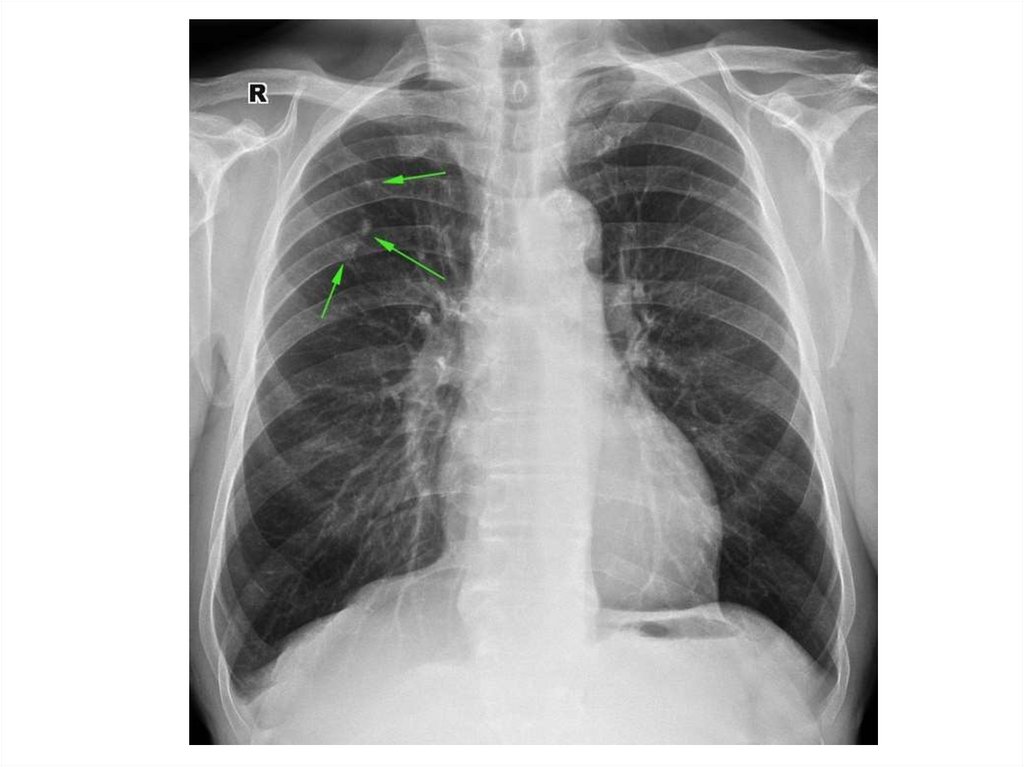

Пневмоторакс

Эмфизема

Пневмония